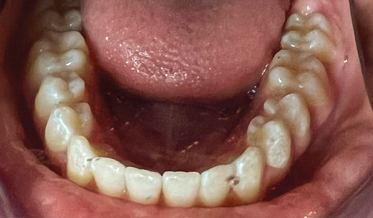

Digital Workflow as an Aid to Complex Multidiscipline Dental Treatment for Improved Esthetics

Fred A. Puccio, DDS; and Gregori M. Kurtzman, DDS